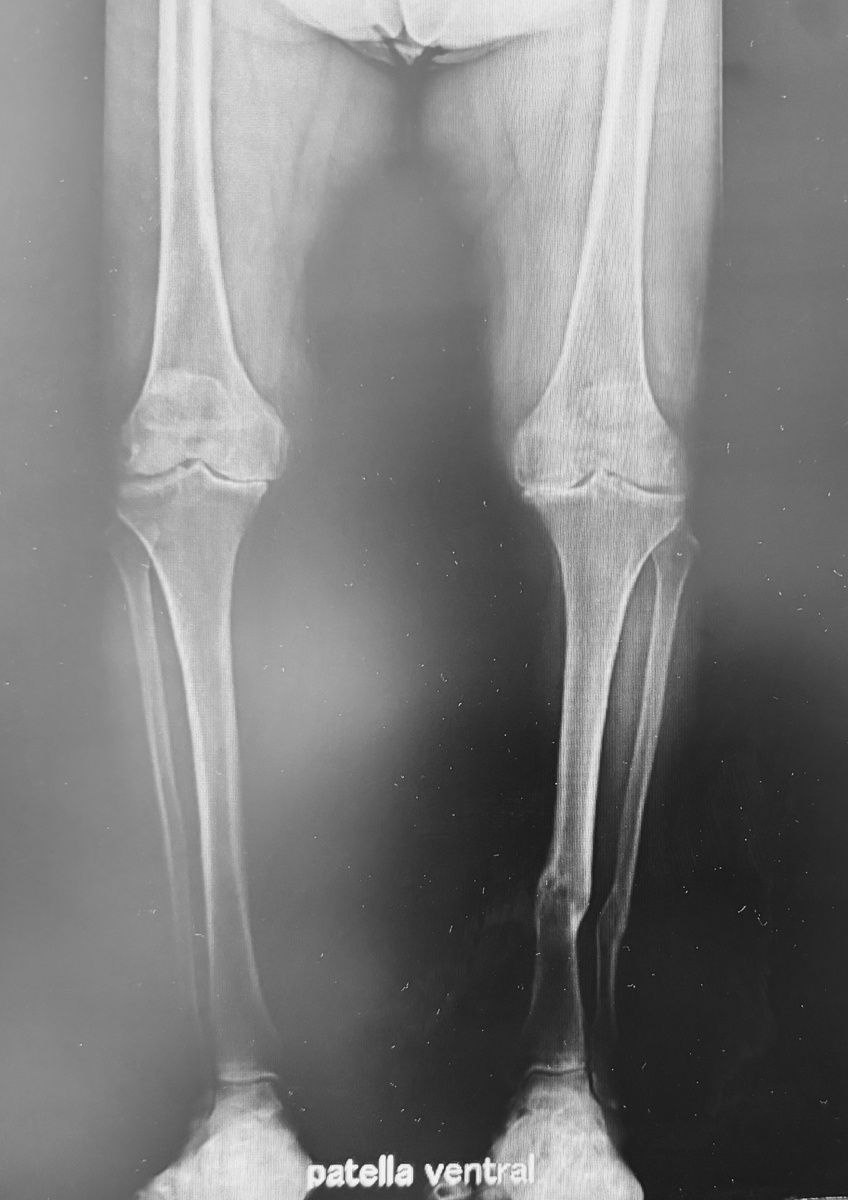

Самый свежий пример. Пациентке 85 лет. Двусторонний гонартроз (артроз коленных суставов), выраженная О-образная деформация ног.

-2

Боль в коленях мешает…. работать. Да-да. Дама продолжает работать - преподавать, да еще и собственной фирмой руководит! Всё не было времени на себя, но боль - дело такое, ни строить, ни жить не позволяет.

-3

На консультации договорились, что меняем один сустав, и, как только терапевтические показатели приходят в норму - второй. При таких деформациях мы выпрямляем и удлиняем ногу, и, если вторая долгое время остается деформированной, это негативно сказывается на оперированной. Поскольку здесь был довольно сложных подготовительный этап, я был уверен, что перерыв будет месяца три.

Было-стало:

-5

Кстати, слева еще сросшийся довольно свежий перелом костей голени:

-6